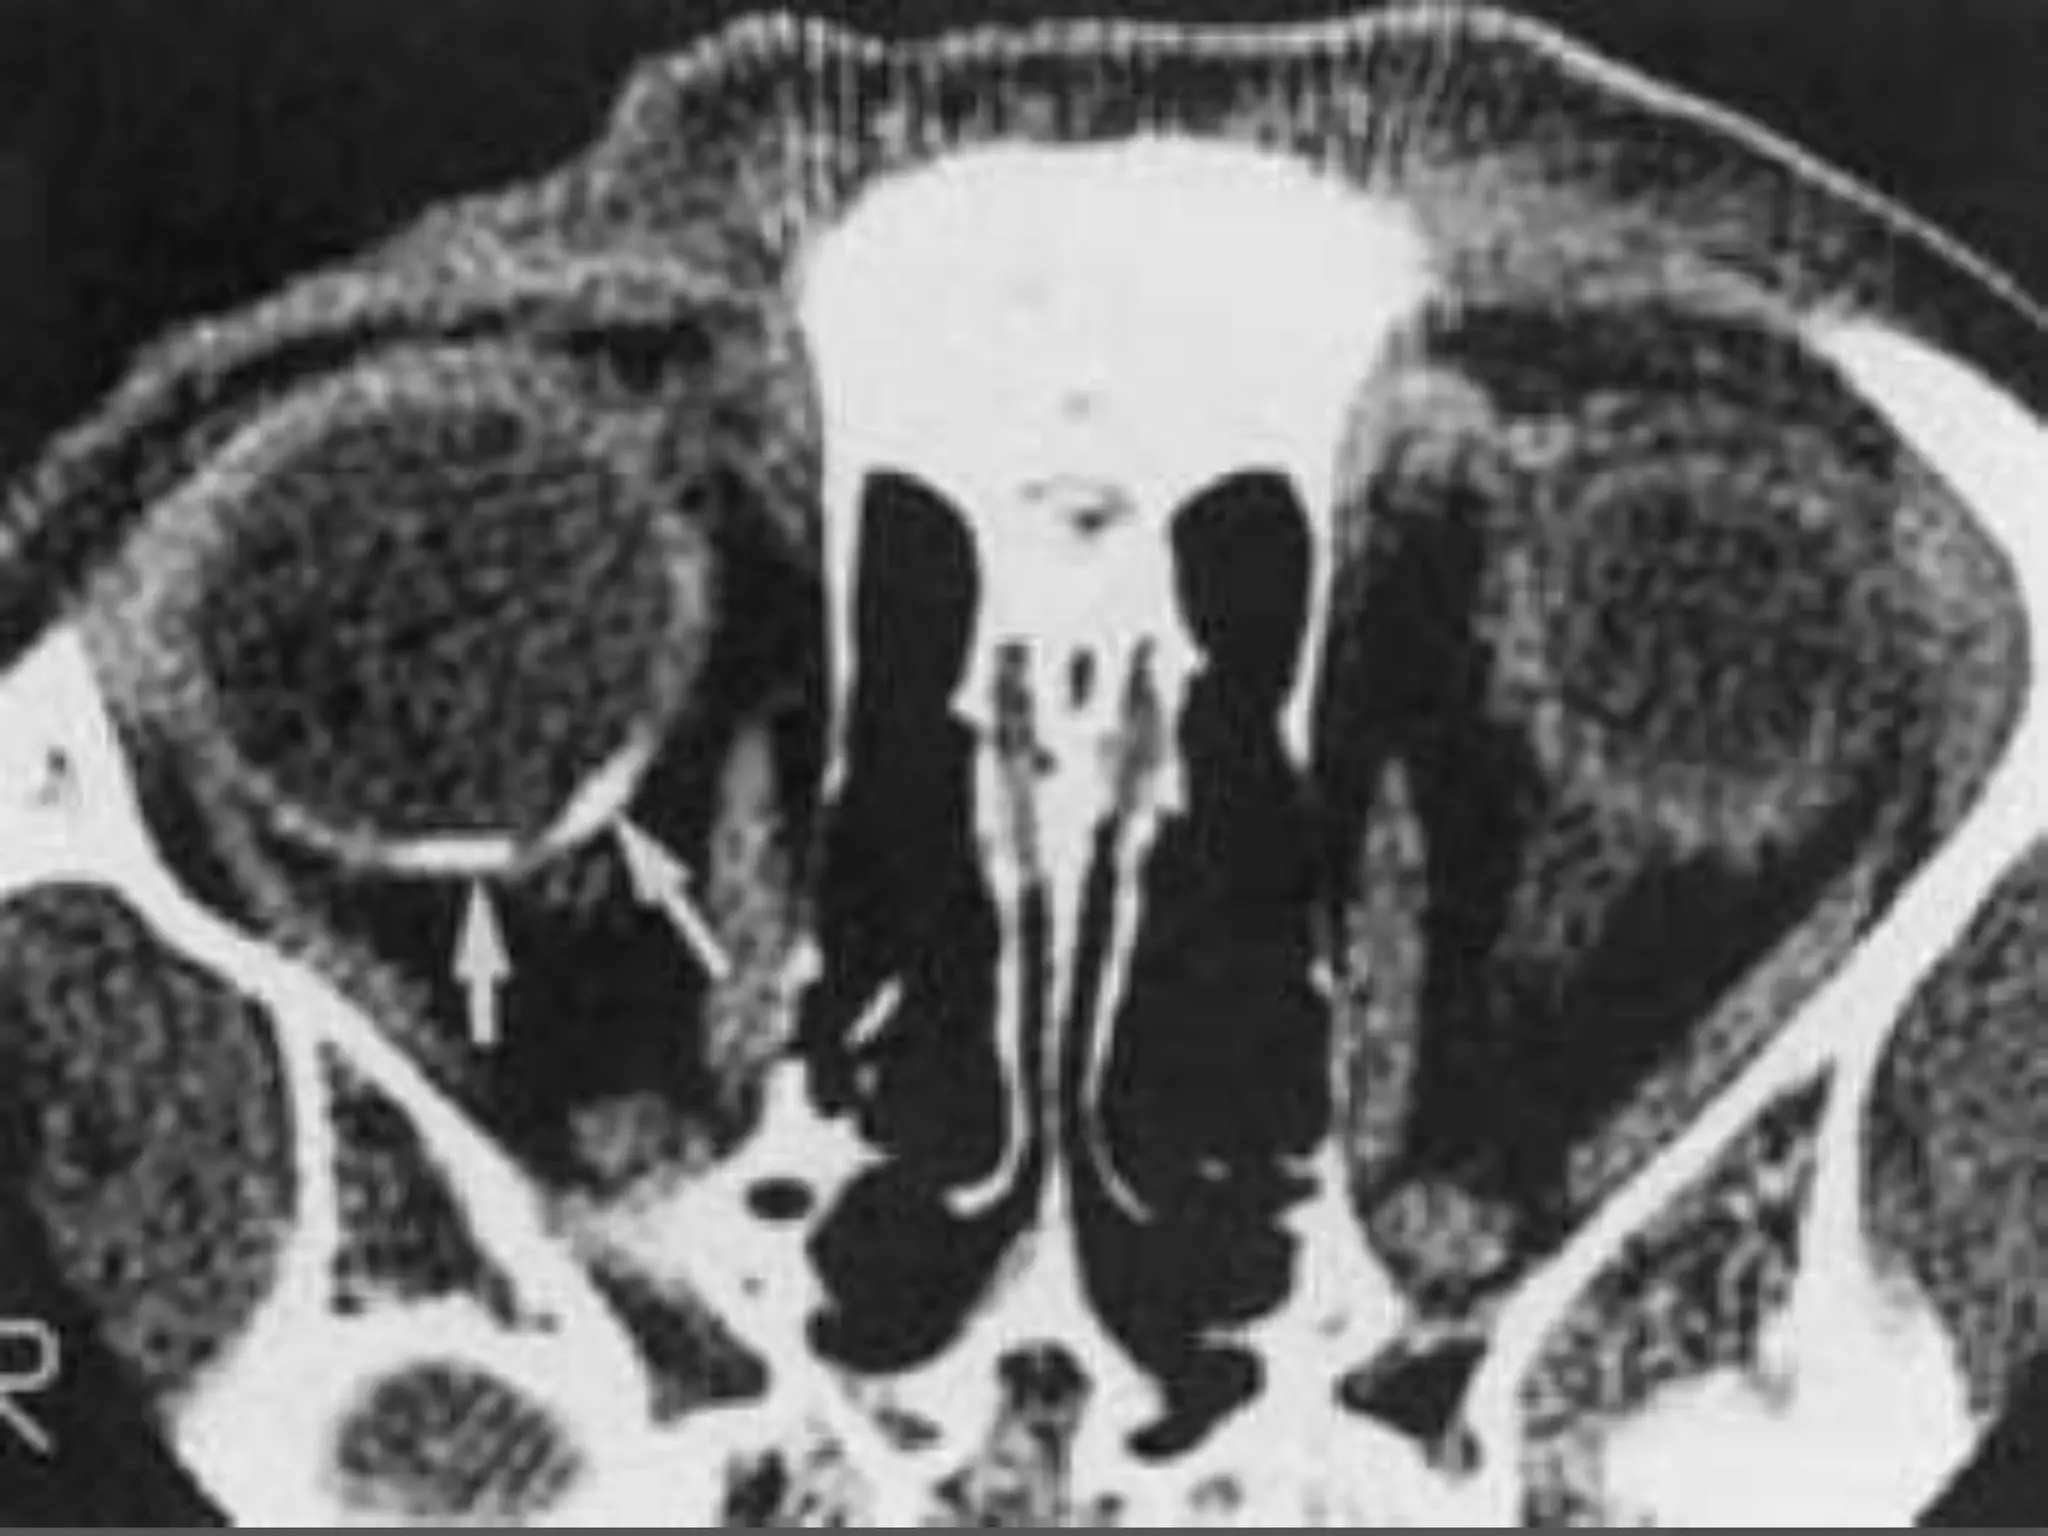

• #26 Retinoblastoma. A, Leukokoric left eye (whitish papillary reflex). B, Axial CT scan shows a large calcified intraocular mass (M). Note the noncalcified component (arrowhead). C, Axial T1WI shows a relatively hyperintense infiltrative mass (arrows). D, Axial T2WI shows a hypointense infiltrative mass (M). Note the extension along the temporal aspect of the globe (arrows).

• #27 Retinoblastoma with optic nerve involvement. A, Enhanced, fat-suppressed, axial T1-weighted MR image shows marked enhancement of a retinoblastoma (R) with extension into the optic nerve (arrow). B, Photomicrograph of an enucleated eye showing the tumor (T) as well as extension into the optic nerve head (arrow). (Courtesy of D. Ainbinder, MD, Tacoma, WA.)

• #28 Tetralateral retinoblastoma. A, Axial T2-weighted MR image shows bilateral retinoblastoma (arrows). B, Enhanced axial T1-weighted MR image shows a markedly enhancing suprasellar mass (m). Note the subarachnoid spread of the tumor, seen as leptomeningeal enhancement along the sylvian fissures (arrows). C, Enhanced axial T1-weighted MR image shows marked enhancement of a pinealoblastoma (arrow). D, Enhanced sagittal T1-weighted MR image obtained a few months later shows diffuse distal spinal cord (C ) and subarachnoid metastases (arrows).